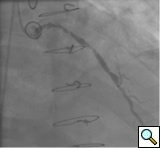

PCI of the vein and arterial grafts have unique challenges. For any PCI, guide support is very important for successful balloon and stent delivery. In a tortuous vein graft with a steep angle, advancement of a stent can be very difficult and challenging. Therefore, it is important to choose the best available catheter before starting PCI. Similar to the right coronary angiography, a JR4 guide catheter is most commonly used in this setting. However, Amplatz guide catheters for left vein grafts and multipurpose catheters for right vein grafts are better choices in certain anatomy. In Figure 8 and Figure 10 two examples of poor guide support in two vein graft interventions can be seen. Initially, a JR4 guide was used for PCI of the vein graft supplying the left anterior descending artery (LAD) without any success. However, after changing the guide to an Amplatz left 2 guide catheter, we achieved excellent support without any difficulty in advancing two stents (Figure 9). In Figure 10, difficulty is illustrated in engaging the vein graft ostium supplying the right coronary artery with a JR4 catheter. This vein graft has a very steep inferior take off from the aorta. After changing the guide to a multipurpose catheter, we were able to deliver three stents successfully without any difficulties (Figure 11). Similar challenges exist in the treatment of the left IMA or right IMA. These arterial grafts can be extremely tortuous making stent delivery very difficult. It may be necessary to use short length stents for a better deliverability or stents with lowest profile. Usually, similar to the native coronary intervention, a 6 French guide is appropriate for the routine use.